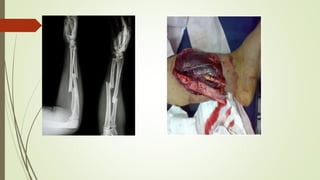

FRATURAS

Ruptura total ou parcial da estrutura óssea

Podem ser classificadas em fechada ou exposta

SINAIS E SINTOMAS

 Dor

 Inchaço



 Incapacidade Funcional

 Deformidade

 Crepitação

 Em fraturas expostas pode haver rompimento da pele e exposição óssea.

CONDUTA

 Imobilização de articulação acima e abaixo do local

 Buscar a posição mais confortável para o paciente

 Em fraturas expostas realizar curativo com compressa limpa e úmida,

 Não tentar alinhar osso